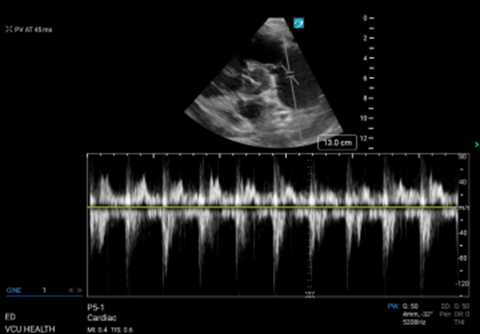

Calculating pulmonary acceleration time

Pulmonary acceleration time (PAT); or pulmonary artery acceleration time (PAAT)) is the time it takes for blood flow into the pulmonic trunk to reach maximum velocity. PAT is shorter when pulmonary arterial resistance is increased. Starting in a parasternal short view, the probe is fanned superiorly to find the RVOT above the aortic valve. The pulsed wave (PW) doppler gate is then placed just proximal to the pulmonic valve and velocity tracing generated. (Figure 3) PAT is the time from the start of flow to the peak, normal values being greater than 60msec. An abnormally short PAT (<60msec) suggests an abnormally increased pulmonary arterial resistance. The patient in this case had a PAT of 45ms, and an abnormal waveform demonstrating a mid-systolic notch. While the distinction can be difficult, an early systolic (ESN) occurs in the first half of systole and is more indicative of PE, while a mid- or late-systolic notch points towards PAH.

Figure 3. PW doppler of RVOT with measurement of PAT.